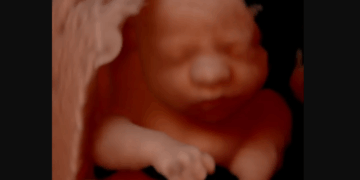

“You really think that this is an image of a human being?” Abortion advocates will often ask this question while showing an image of a dog embryo. (click here to see an example image) If you say yes, the abortion advocate will ruthlessly mock…

Planned Parenthood is drawing sharp criticism from pro-life advocates after comparing an unborn baby in early pregnancy to dryer lint. The crass comparison came in a blog post aimed at women who have taken abortion pills. In an April 10 post…